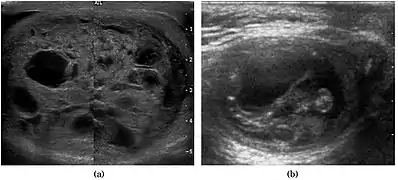

Fig. 3. Seminoma. (a) Seminoma usually presents as a homogeneous hypoechoic nodule confined within the tunica albuginea. (b) Sonography shows a large heterogeneous mass occupying nearly the whole testis but still confined within the tunica albuginea, it is rare for seminoma to invade to peritesticular structures.

Approximately 95% of malignant testicular tumors are germ cell tumors, of which seminoma is the most common. It accounts for 35%–50% of all germ cell tumors. Seminomas occur in a slightly older age group when compared with other nonseminomatous tumor, with a peak incidence in the fourth and fifth decades. They are less aggressive than other testicular tumors and usually confined within the tunica albuginea at presentation. Seminomas are associated with the best prognosis of the germ cell tumors because of their high sensitivity to radiation and chemotherapy.

Seminoma is the most common tumor type in cryptorchid testes. The risk of developing a seminoma is increased in patients with cryptorchidism, even after orchiopexy. There is an increased incidence of malignancy developing in the contralateral testis too, hence sonography is sometimes used to screen for an occult tumor in the remaining testis. On US images, seminomas are generally uniformly hypoechoic, larger tumors may be more heterogeneous [Fig. 3]. Seminomas are usually confined by the tunica albuginea and rarely extend to peritesticular structures. Lymphatic spread to retroperitoneal lymph nodes and hematogenous metastases to lung, brain, or both are evident in about 25% of patients at the time of presentation.